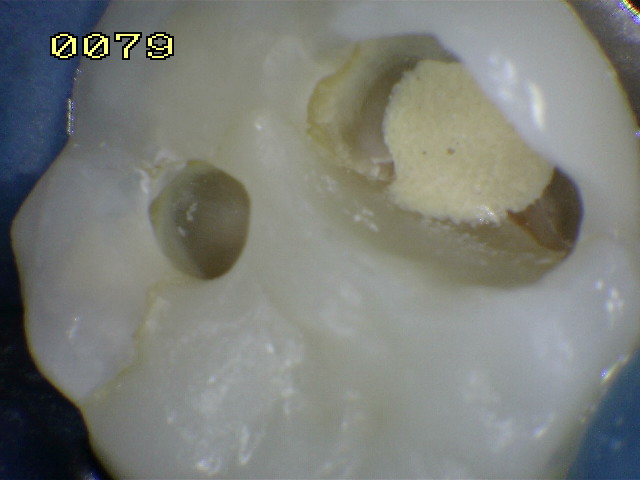

Observe el remanente de esmalte en la ángulo axio gingival de la cavidad y la desadaptación de la matriz metálica

Observe la recidiva de caries debajo de la resina compuesta remanente en pieza dental endodonciada

Observe la dentina desorganizada que cambia de color, esta debe ser eliminada